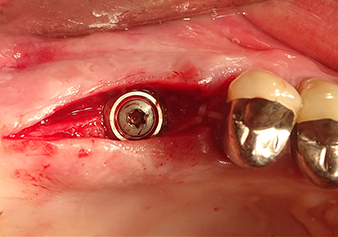

Имплантация и протезирование

Для перемещения аугментационного материала в направлении верхнечелюстной пазухи атравматично, имплантат вводился очень медленно вручную (рис. 9). При этом мембрана еще раз выталкивалась в краниальном направлении. Через два месяца место операции зажило без раздражения. Через шесть месяцев рентгеновский контроль показал значительное увеличение помутнения, что свидетельствует об оссификации (рис. 10). Протезирование было проведено металлокерамической коронкой.

В авторской практике мембрана обычно поднимается в два этапа. В качестве альтернативы подходит метод, указанный производителем. В этом случае сначала подготавливается ложе для имплантата, и только затем при помощи инструмента Z35P в небольшом объеме вскрывается костное дно пазухи. В результате очень атравматичного метода пациент не испытывал послеоперационной боли и смог вернуться к работе на следующий день. В практике автора это касается 90% пациентов.